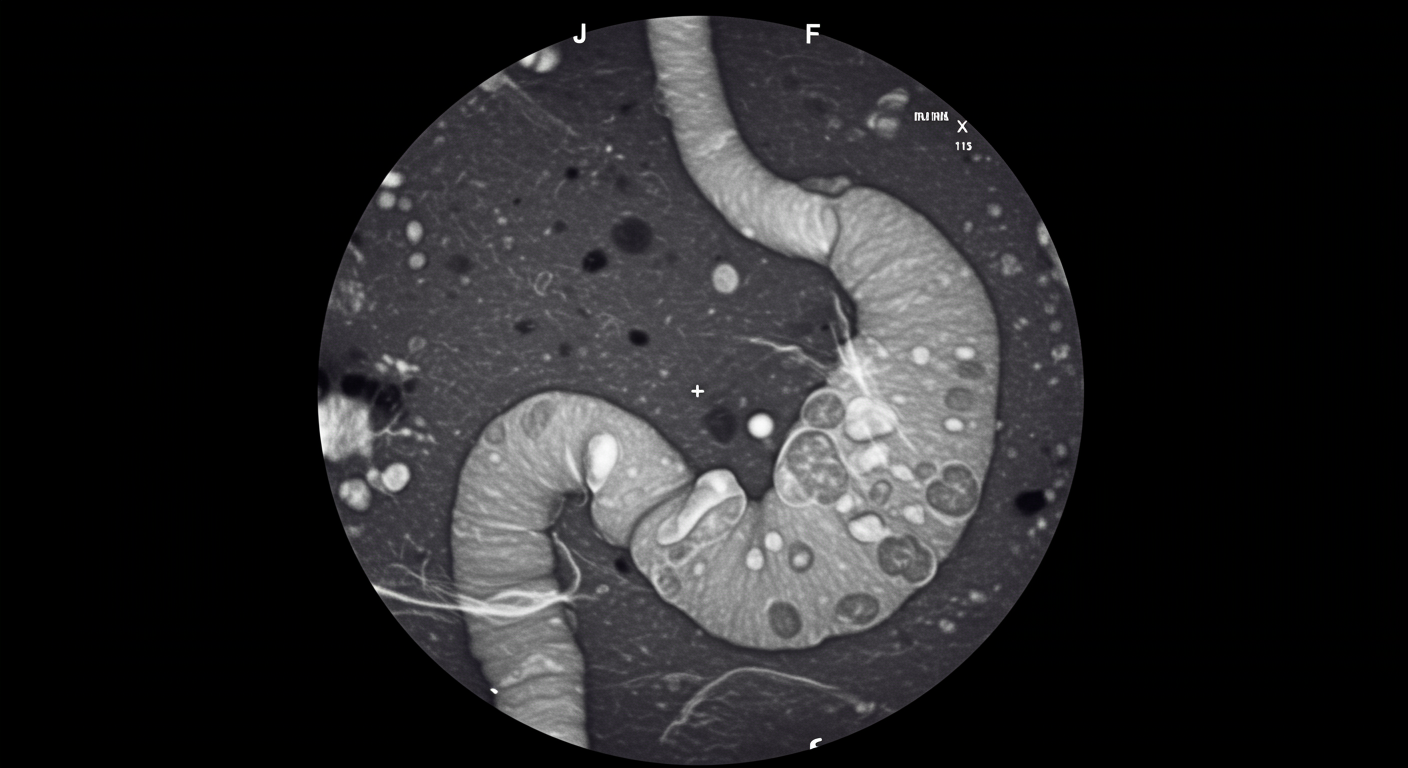

This case series documented two patients with large PPI-induced gastric polyps (>2 cm) who achieved complete polyp regression within 2 months of proton pump inhibitor discontinuation. The cases included detailed endoscopic documentation and histological analysis to confirm both the PPI-induced nature of the polyps and their complete resolution.

The research demonstrates that even large, concerning-appearing polyps can undergo rapid and complete regression when the underlying hypergastrinemia is addressed through PPI cessation.

- Endoscopic confirmation: Serial endoscopy documented complete resolution

- Histological findings: Confirmed hyperplastic nature without dysplasia